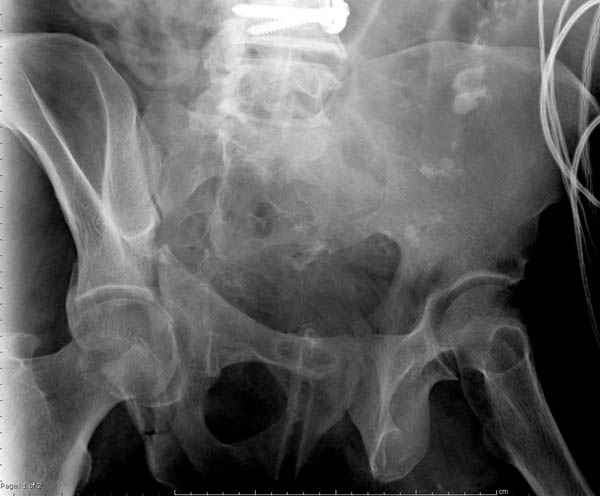

Дополнительно имеется перелом ацетабулума: задняя

колонна с полупоперечным переломом, и переломы костей лица.

На седьмой день зафиксирован перелом ацетабулума через задний доступ. Перед операцией для профилактики DVT, IVC фильтер, также получает Lovenox.

Извиняюсь за качества снимков, обычный больной в 300 фунтов, портативным ренген аппаратом не пробить.

Полную нагрузку разрешаем в 12 недели, хотя движения в суставе с первых дней.

Снимки здесь....